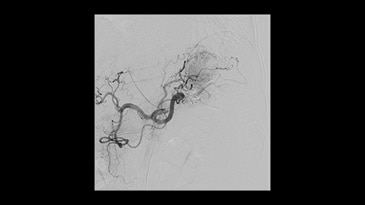

Klinik Görüntüler

-

Aortic procedure